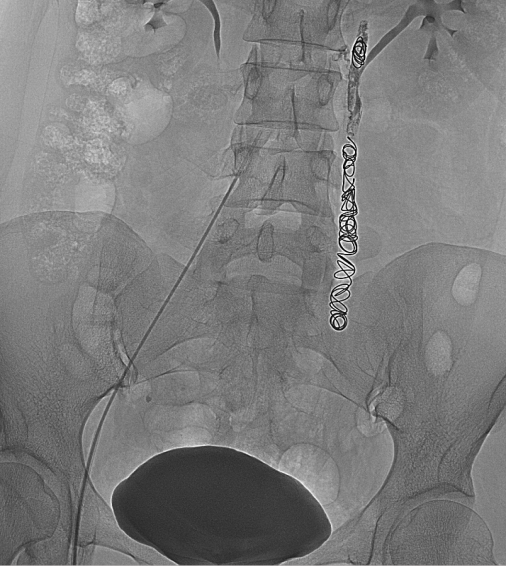

3.经皮导管逆行卵巢静脉造影术

目前认为是盆腔淤血综合征诊断金标准。

盆腔淤血综合征的介入治疗是在局部麻醉状态下,通过股静脉穿刺或颈静脉,引入导丝、导管,插入到盆腔静脉,进行盆腔静脉造影及予以硬化剂、金属弹簧圈等予以栓塞,将有病变扩张的盆腔静脉进行封闭,从而达到治疗的目的。

盆腔淤血综合征的介入治疗具有安全性高、创伤小、效果确切、不影响月经及生育的特点。